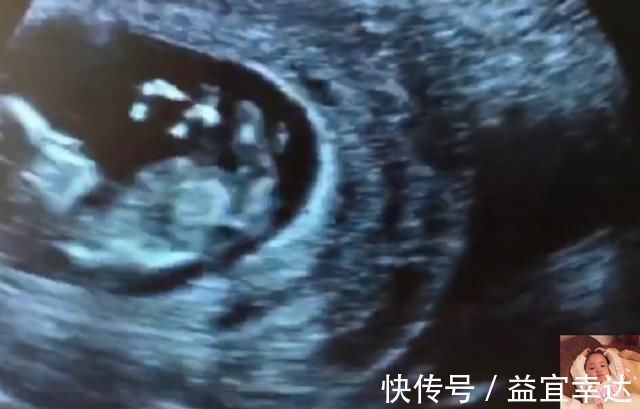

7)好渴,喝口水吧

尿完以后,胎宝宝发现自己有些口渴,于是张开嘴巴开始喝羊水。是的,尿液就是胎宝宝的羊水,但别嫌脏,里面是无菌环境,一切都是干净的。

胎宝宝在喝水的时候,孕妈就会觉得肚子里的宝宝在一跳一跳的,就像打嗝一样。